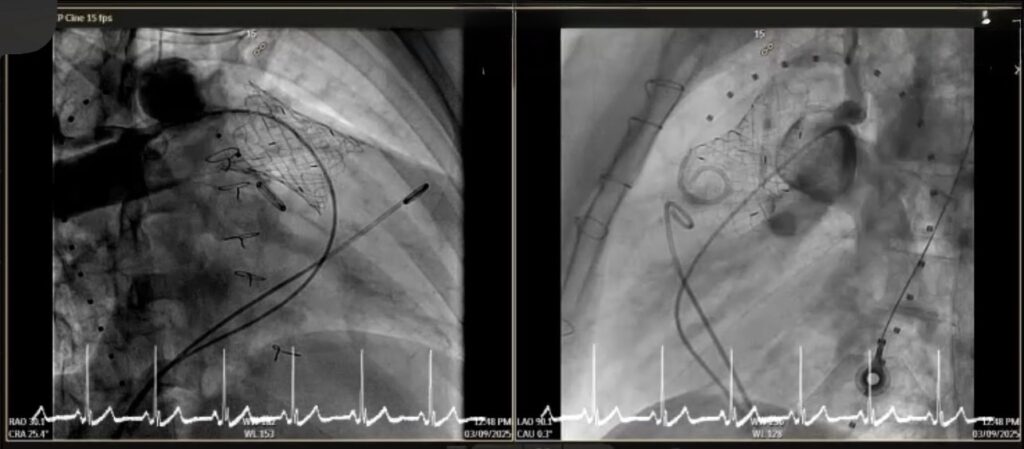

คณะแพทยศาสตร์ มช. สร้างความสำเร็จทางการแพทย์ ด้วยการรักษาโรคลิ้นหัวใจพัลโมนิกรั่ว (Pulmonary valve regurgitation) ผ่านสายสวน ในผู้ป่วยหญิงไทย อายุ 22 ปี ที่มีประวัติผ่าตัดรักษาภาวะ Tetralogy of Fallot มาก่อน และมีอาการของลิ้นพัลโมนิกรั่วรุนแรง

การใส่ลิ้นหัวใจพัลโมนิกเทียมผ่านสายสวนหัวใจ (Transcatheter pulmonary valve implantation; TPRI ) ในครั้งนี้ ทำผ่านทางหลอดเลือดดำใหญ่ บริเวณขาหนีบ จึงไม่ต้องผ่าตัดเปิดทรวงอก โดยกระบวนการรักษาและพักฟื้นผ่านไปได้ด้วยดี ไม่พบภาวะแทรกซ้อน ผู้ป่วยสามารถออกจากโรงพยาบาล 2 วันภายหลังการรักษา นับเป็นหนึ่งในความก้าวหน้าของนวัตกรรมการแพทย์เพื่อใช้รักษา ลดความเสี่ยงของภาวะแทรกซ้อนต่างๆ รวมถึงยกระดับคุณภาพชีวิตของผู้ป่วยได้

การแก้ไขลิ้นหัวใจพัลโมนิกรั่วมี 2 วิธี คือ การผ่าตัดเปิดทรวงอกเพื่อใส่ลิ้นหัวใจพัลโมนิกเทียม และ การใส่ลิ้นพัลโมนิกผ่านทางสายสวนหัวใจ การเปลี่ยนลิ้นทั้งสองวิธีนี้เมื่อเวลาผ่านไป 10-20 ปี ลิ้นพัลโมนิกเทียมจะมีโอกาสเสื่อมอีก ทำให้ผู้ป่วยประมาณ 1 ใน 3 จำเป็นต้องเปลี่ยนลิ้นหัวใจซ้ำอีกครั้ง ซึ่งในผู้ป่วยบางรายอาจจะต้องการการใส่ลิ้นพัลโมนิกเทียมไม่ว่าจะโดยการผ่าตัดหรือผ่านทางสายสวน 2-3 ครั้งในช่วงชีวิตหนึ่ง

การผ่าตัดเปิดทรวงอกในแต่ละครั้ง จะก่อให้เกิดพังผืด (fibrous adhesion) เพิ่มความยากลำบาก และความเสี่ยงในการผ่าตัดมากขึ้น การรักษาผ่านทางสายสวนจึงเป็นทางเลือกที่จะลดความเสี่ยงนี้ลง อีกทั้งยังสามารถใส่ลิ้นพัลโมนิกเทียมชิ้นใหม่ทับแทนชิ้นเก่าได้ (valve in valve procedure)

การรักษาผ่านทางสายสวนครั้งนี้ได้รับความร่วมมือจากสหสาขาวิชาชีพ อาทิเช่น ศัลยแพทย์โรคหัวใจ ทรวงอก และหลอดเลือด กุมารแพทย์โรคหัวใจ อายุรแพทย์โรคหัวใจ วิสัญญีแพทย์ รังสีแพทย์ นักเทคโนโลยีหัวใจและทรวงอก รังสีแพทย์และนักรังสีการแพทย์ เจ้าหน้าที่และพยาบาลห้องสวนหัวใจ ห้องผ่าตัดศัลยกรรมทรวงอก หอผู้ป่วยวิกฤตศัลยกรรมหัวใจหลอดเลือด หอผู้ป่วยพิเศษ 5 พยาบาลหน่วยโรคหัวใจเด็กและผู้ใหญ่